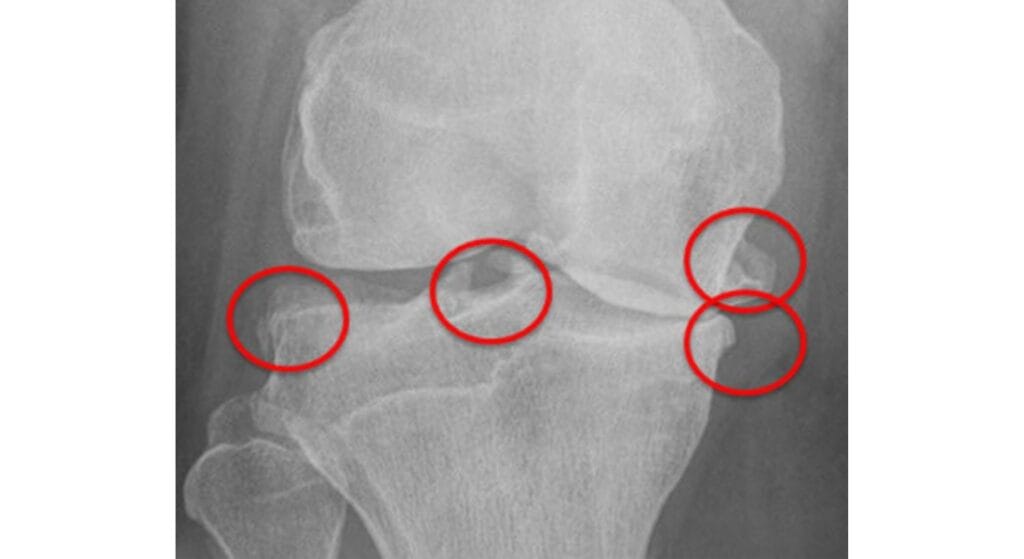

- X-quang khớp gối: Phương pháp thường dùng nhất, giúp quan sát được các mỏm gai xương, khe khớp hẹp, hình ảnh thoái hóa.

- MRI (Cộng hưởng từ): Được chỉ định khi nghi ngờ tổn thương sụn khớp, dây chằng hoặc phần mềm quanh khớp.